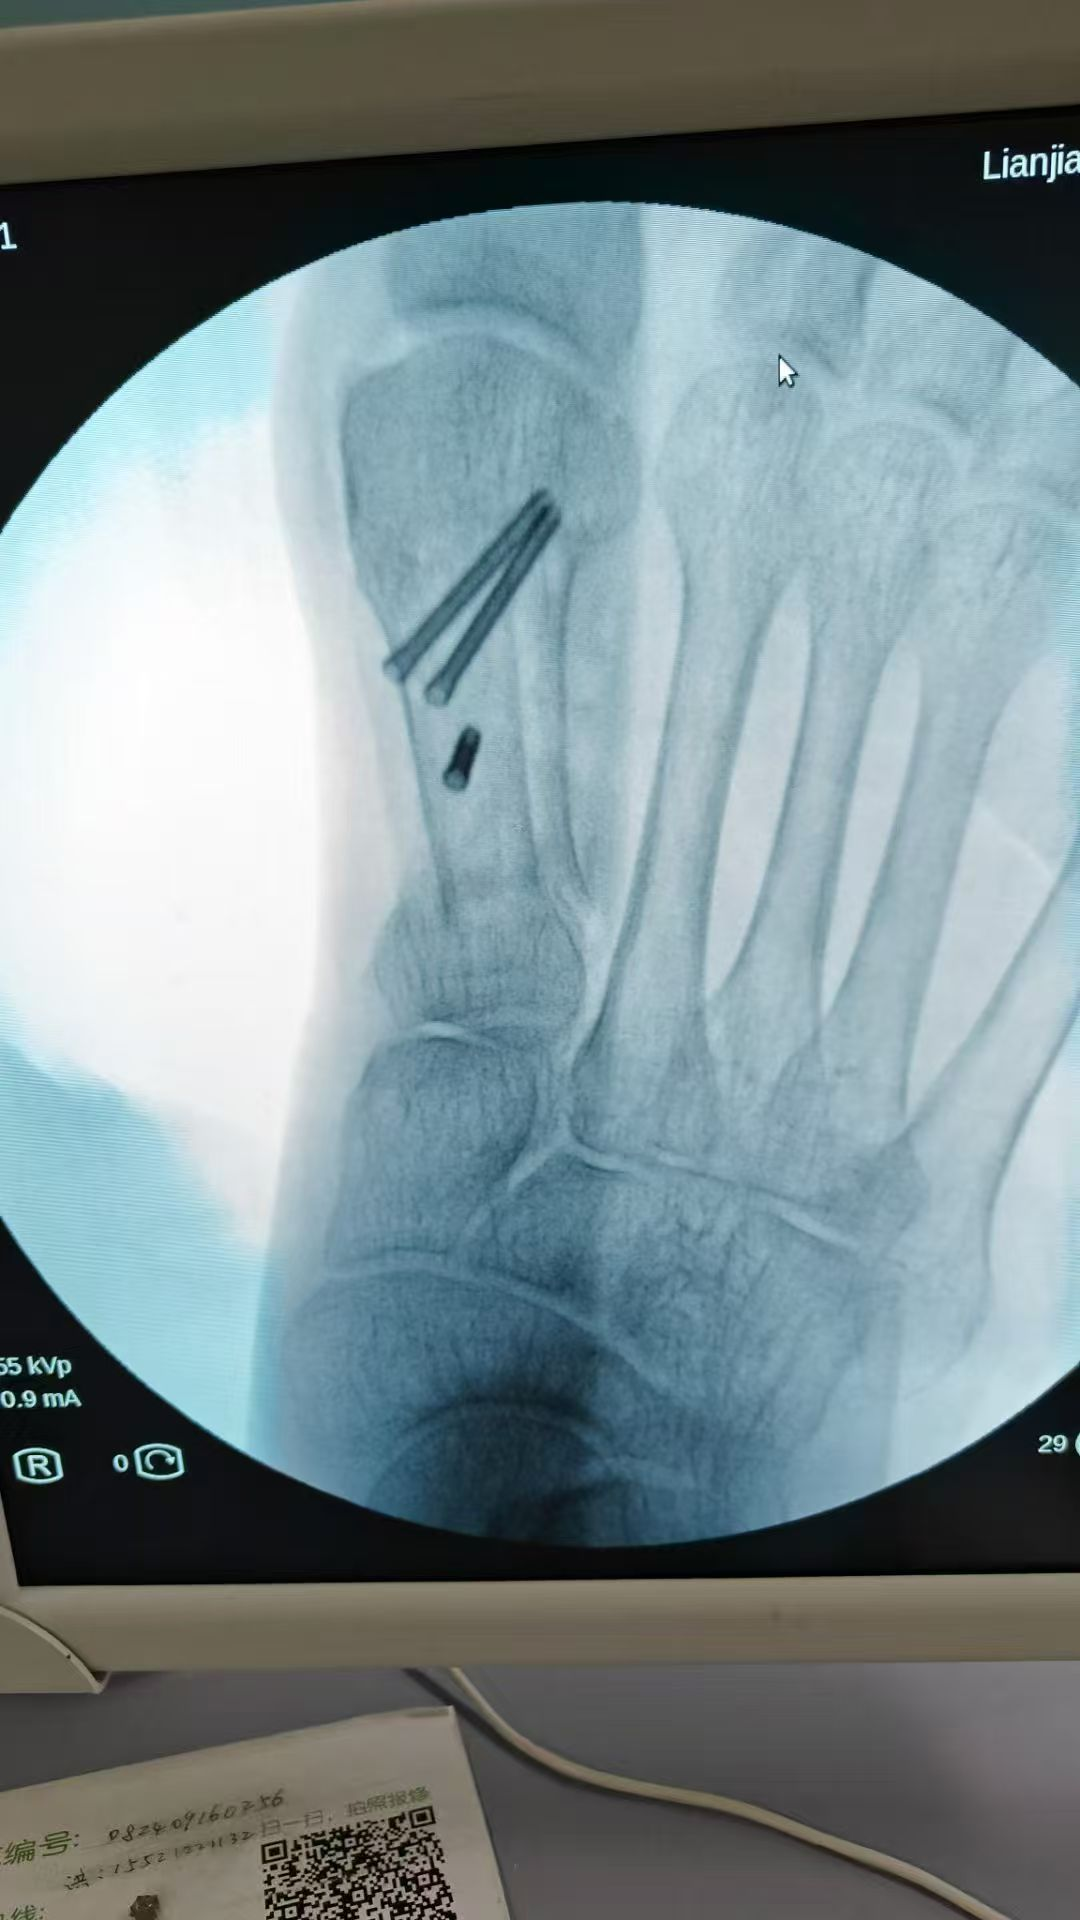

图片图片图片

跟骨粉碎性骨折闭合复位微创经皮穿针内固定